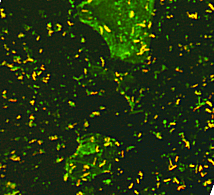

Микробактерии Mycobacterium tuberculosis обладают невероятно низкой инфекционной дозой — менее 10 микроорганизмов для инициирования заболевания. Бактерии имеют длительный период инкубации: от двух до двенадцати недель с диапазоном от четырнадцати дней до нескольких десятилетий.

Они обладают способностью, как к скрытости, так и к инициированию активной формы заболевания. Микобактерии, вдыхаемые хозяином, заражают легкие, и поглощается макрофагами альвеол. После этого они длительное время могут оставаться бездействующими или начинать размножаться внутри указанных клеток, что вызывает появление открытой инфекции.

Микробактерии, попадая в организм, распространяются бронхолегочным, гематогенным и лимфогенным путем. В легких начинается образование отдельных или множественных бугорков. При закрытой форме туберкулеза микробактерии размещаются внутри этих бугорков и находятся в изолированном состоянии, не выделяя инфекции в окружающую среду. В этом случае окружающие не могут заразиться.